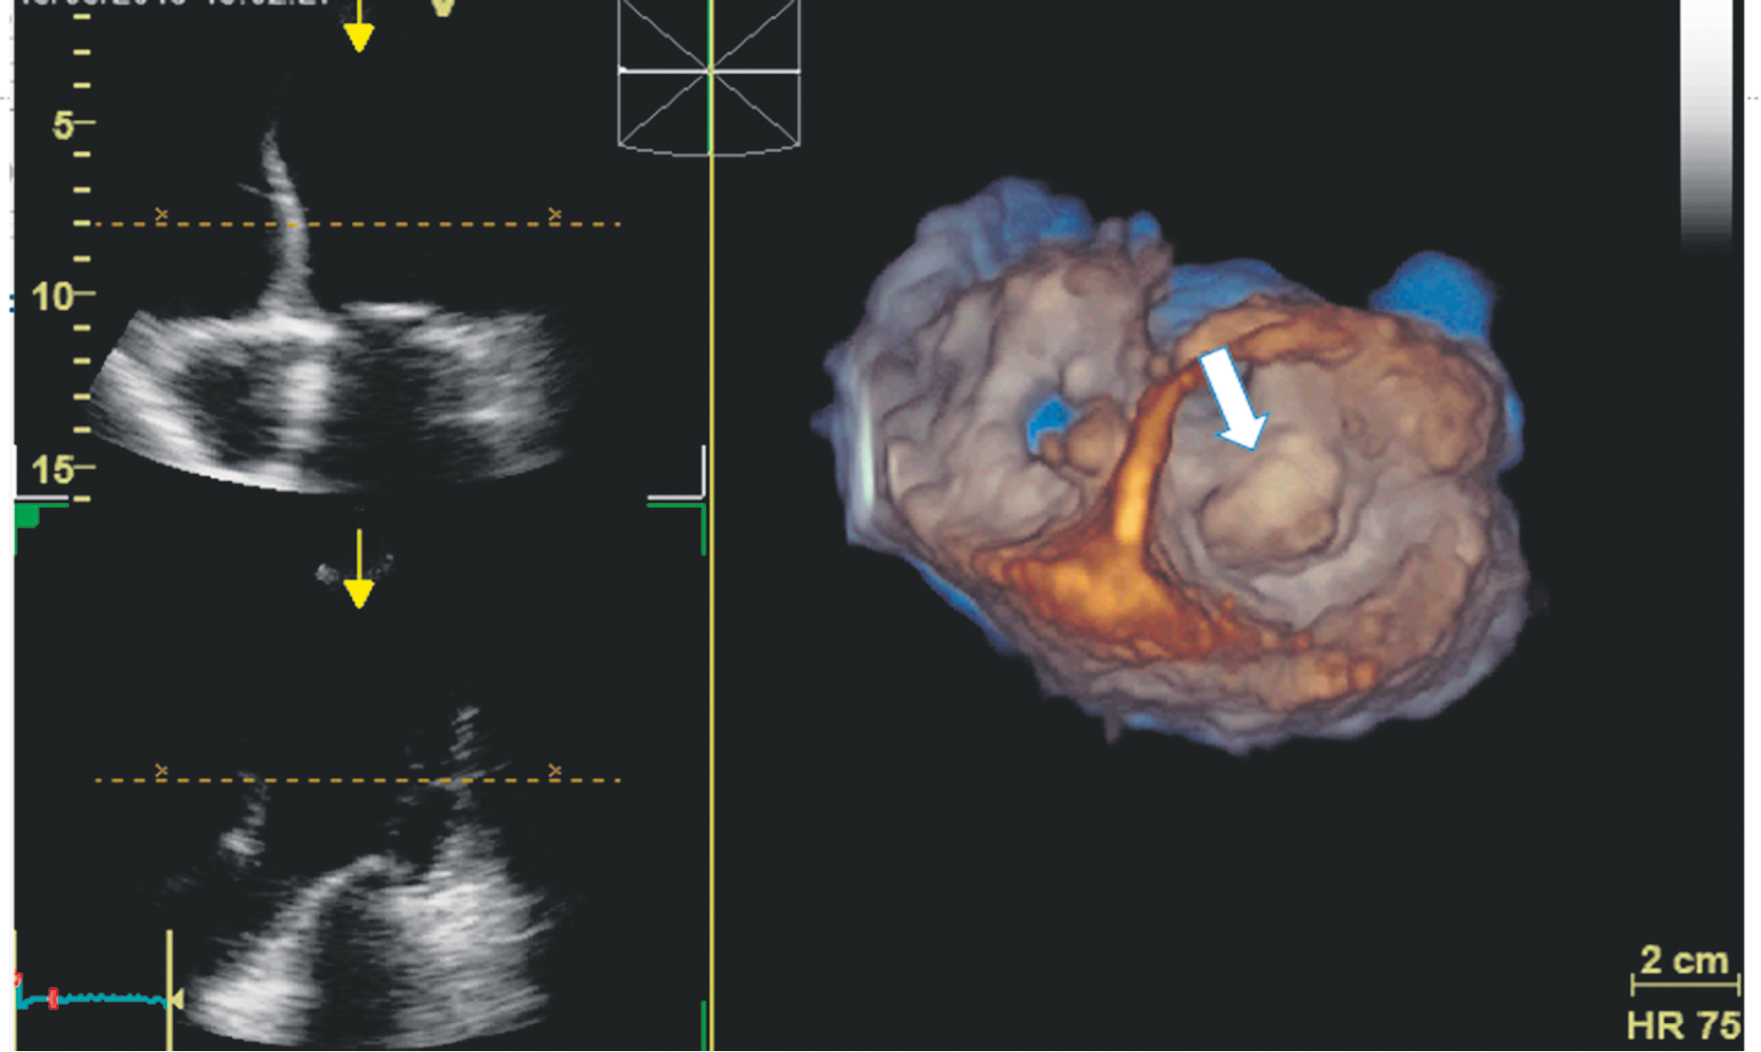

EchoCG was performed using modern technologies of three-dimensional image reconstruction and Mitral Valve Quantification model on Vivid-9 ultrasound device. The results showed that mitral regurgitation was mild [16]. The effective regurgitation orifice area was 0.18 cm2, and the regurgitation volume was 20 mL. Both mitral valve leaflets were myxomatous, thickened, and prolapsed up to 8 mm into the LA cavity (Fig. 1–3). The prolapse was polysegmental (Fig. 4). Signs of MAD (absence of myocardial tissue up to 9 mm under the posterior mitral valve leaflet) were revealed (Fig. 1, 2).

Fig. 3. Three-dimensional reconstruction of the mitral valve. The white arrow indicates the elongated and prolapsed mitral valve leaflets

Fig. 4. Three-dimensional model of the mitral valve. Mapping in red shows the prolapse of all segments of both leaflets at end-systole